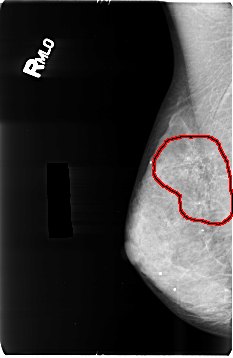

B_3496_1.RIGHT_MLO

FILE: B_3496_1.RIGHT_MLO.OVERLAY

TOTAL_ABNORMALITIES 1

ABNORMALITY 1

LESION_TYPE CALCIFICATION TYPE PUNCTATE-AMORPHOUS DISTRIBUTION REGIONAL

ASSESSMENT 4

SUBTLETY 4

PATHOLOGY BENIGN

TOTAL_OUTLINES 1

BOUNDARY